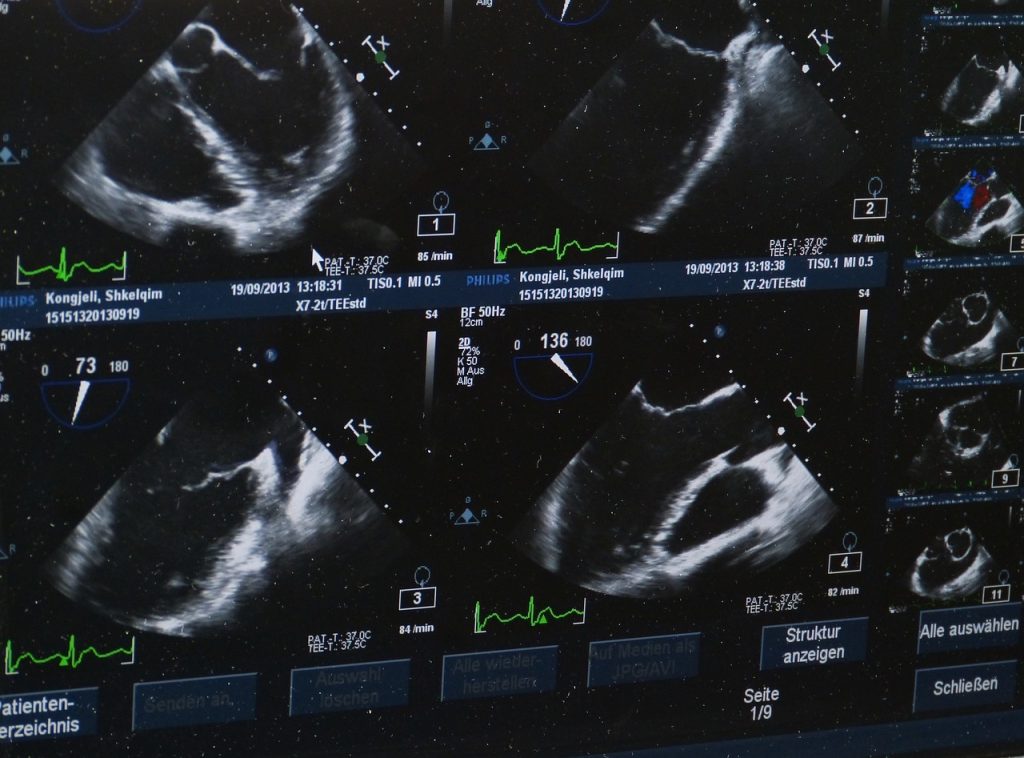

Les écoles de sonographie offrent la formation nécessaire pour devenir échographiste médical. Les échographistes utilisent des appareils à ultrasons pour observer, détecter et diagnostiquer les problèmes médicaux internes. Les échographistes médicaux diagnostics peuvent également évaluer la croissance et le développement du fœtus. Les écoles d’échographie offrent des programmes de certificat, d’associé et de diplômes qui préparent les étudiants à des carrières en échographie médicale diagnostique. Suivez ces conseils pour choisir une école d’échographie.

Évaluez les installations de l’école

Vous devez réaliser une visite de l’école et une observation des installations qui y sont présentes. Renseignez-vous sur le type d’équipement de laboratoire utilisé, en particulier le type d’appareils à ultrasons. Demandez quel est l’âge de l’équipement et à quelle fréquence l’école met à jour son équipement d’imagerie. Les élèves devraient chercher des écoles dotées de l’équipement le plus récent et mettre leur équipement à jour régulièrement. Assurez-vous de vous renseigner sur les simulateurs d’entraînement aux ultrasons, les mannequins d’essai et autres équipements utilisés pour la formation pratique.